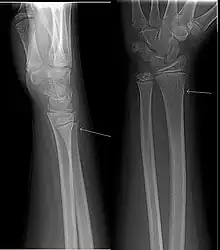

Raio-X de uma fratura em galho verde

Uma fratura em galho verde é uma fratura em um osso jovem e suave que dobra e parcialmente quebra. O nome é uma analogia com um galho verde de madeira que similarmente quebra quando a parte de fora é dobrada.